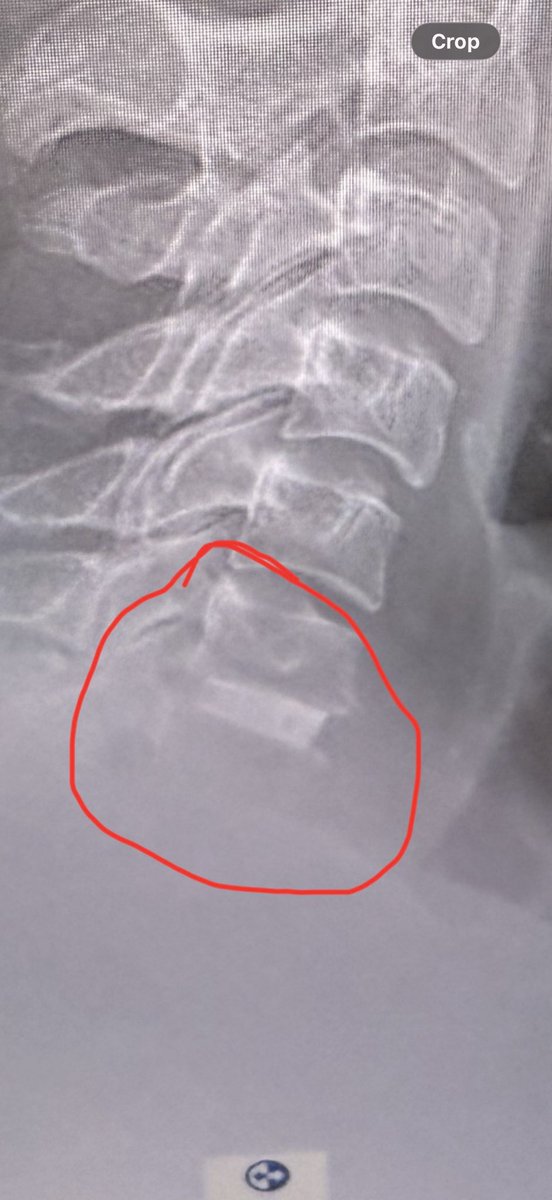

6 weeks today, healing is incredible, tomoz back to driving… physio is hard work! The only issue is the voice very strained by the end of a day (no afternoon meetings 😎) outstanding work by Frimley Park Hospital Another few weeks should be back on the mighty @bmwmotorraduk GSA

Just over a month since the awesome Dr Jandoo & team @FrimleyHealth operated on my spine - the results are incredible and the voice is getting better everyday- looking forward to a full return to my CFAV role @aircadets @ComdtAC @RegComdtLASER